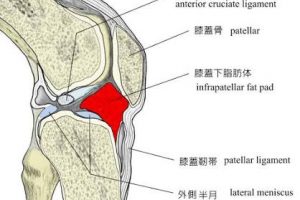

前置きが長くなりましたが、階段を下る時にひざが痛む多くのケースがひざのお皿の下にある「膝蓋下脂肪体(しつがいかいぼうたい)」が硬くなってしまっていることが考えられます。